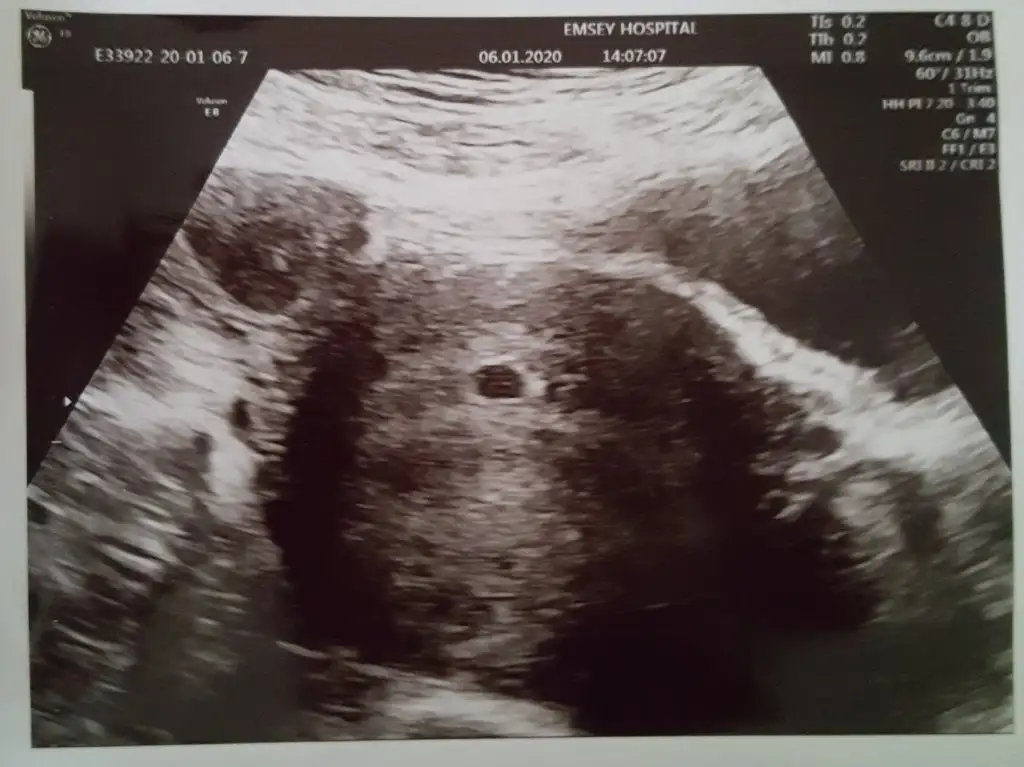

Kanda emin olup kese görmeyi bekleyecekken keseyi şak diye gördüm ya 😃 18. günüm, doktoruma ultrason tarihi almaya gittim, gel şimdi bi bakalım öyle tarih belirleyelim dedi. Dedim doktorcuum görünmez, olsun bakalım yine de dedi. Gördük 😍 ölçecek kadar değil daha, hatta belki ikinci de vardır daha çok erken dedi, ama güzel yere yerleşmiş dedi, bak burda dedi, şaka gibi 😄🎉 hala inanamıyorum. Çok şükür..